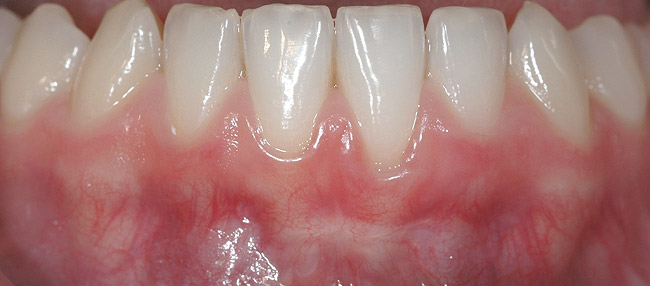

CASE 6 Fig 14. Post-orthodontic Miller Class II recession treated with a combined orthodontic-surgical approach. Clinical view 5 years after first orthodontic treatment showing GR of right lower incisor and a labially prominent root.

Figure 14

Fig 15. Same patient 2 years later showing worsening of GR and inflammation.

Figure 15

A 19-year-old female complaining of gingival recession in the lower right central incisor presented to the authors’ clinic 5 years after completion of orthodontic treatment. The clinical evaluation showed Miller Class II GR accompanied by gingival inflammation (Figure 14). Two years later, despite conservative periodontal treatment, the GR had worsened (Figure 15). The occlusal view shows the presence of a fixed lingual retainer and a significant labial displacement of the root of the affected incisor (Figure 16 and Figure 17). At this stage, orthodontic treatment was considered. The patient was referred for CBCT, which showed no labial bone coverage of the root but 2.5 mm lingual bone thickness at 8 mm distance from the CEJ (Figure 18). After 6 months of orthodontic treatment with fixed appliances (Figure 19), the B-L inclination of the affected tooth was corrected (Figure 20). The frontal clinical view shows narrowing of the GR (Figure 21). Surgical coverage of the exposed root was subsequently performed by connective tissue graft (Figure 22). A long-term stable and esthetic result was achieved (Figure 23).